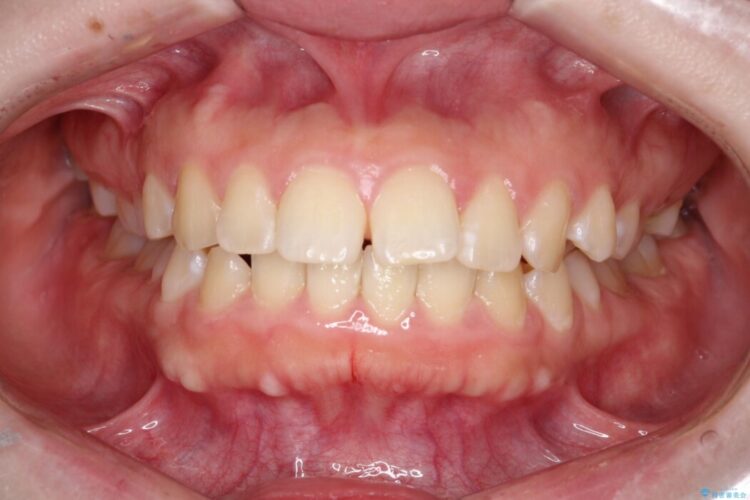

口元の突出感が気になるとご来院された患者様です。

矯正検査の結果、前歯が外側に強く倒れ込んでいる「唇側傾斜(しんそくけいしゃ)」が認められ、口元の突出感の原因になっていました。